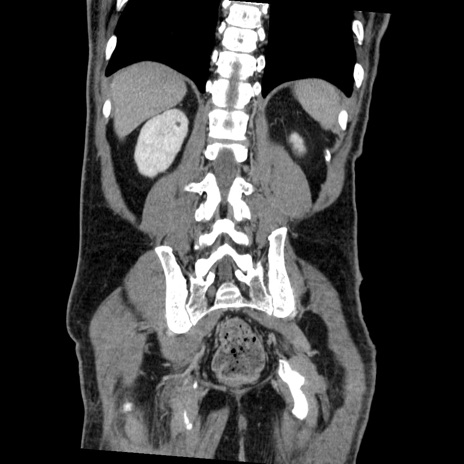

症例22(冠状断像)

【症例】50歳代男性

【主訴】腹痛

【現病歴】AVMからの被殻出血のため回復期リハ病棟入院中。 本日午後3時頃急に下腹部痛が出現した。

【既往歴】AVM、被殻出血、虫垂炎、高血圧

【身体所見】意識晴明、左半身不全麻痺、会話の理解は良好、36.5°C、腹部:膨隆、全体に板状硬、下腹部正中に圧痛点あり、反跳痛-、筋性防御不明、右下腹部にope scar

【データ】WBC 9400、CRP 0.06